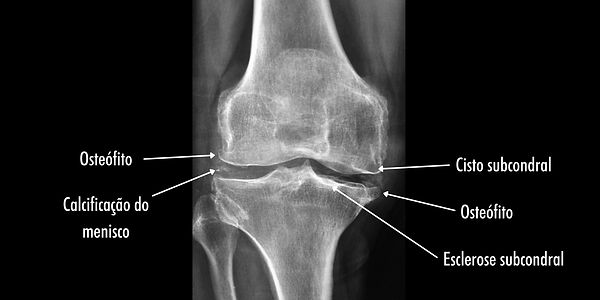

Alguns exames de imagem são importantes para auxiliar o médico no diagnóstico e na classificação da artrose do joelho. O principal deles é a radiografia simples do joelho, que pode mostrar alterações importantes, como as abaixo: